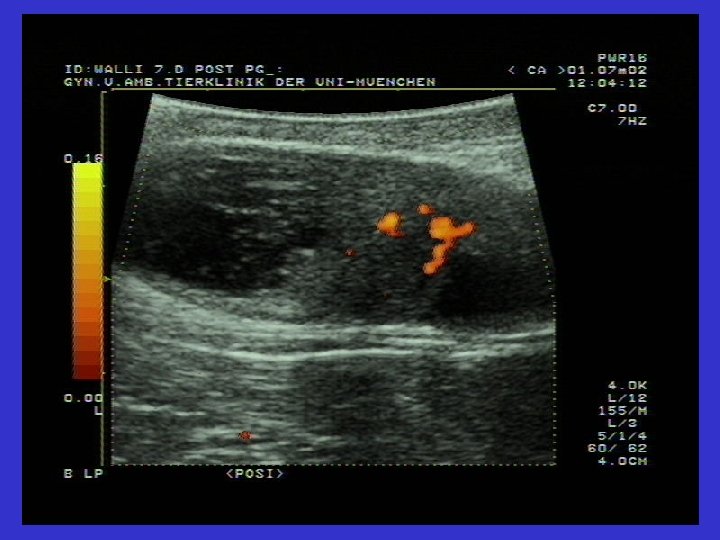

Ovaryum luteal kistlerinin ultrasonografik görüntüsü Solda ovaryum luteal kisti (31 mm). Gri Hipoekojenik alan çepeçevre seçiliyor.

Der praktische Tierarzt, collegium veterinarium XXIX 63 -68 (1999); Zerbe et. Al.